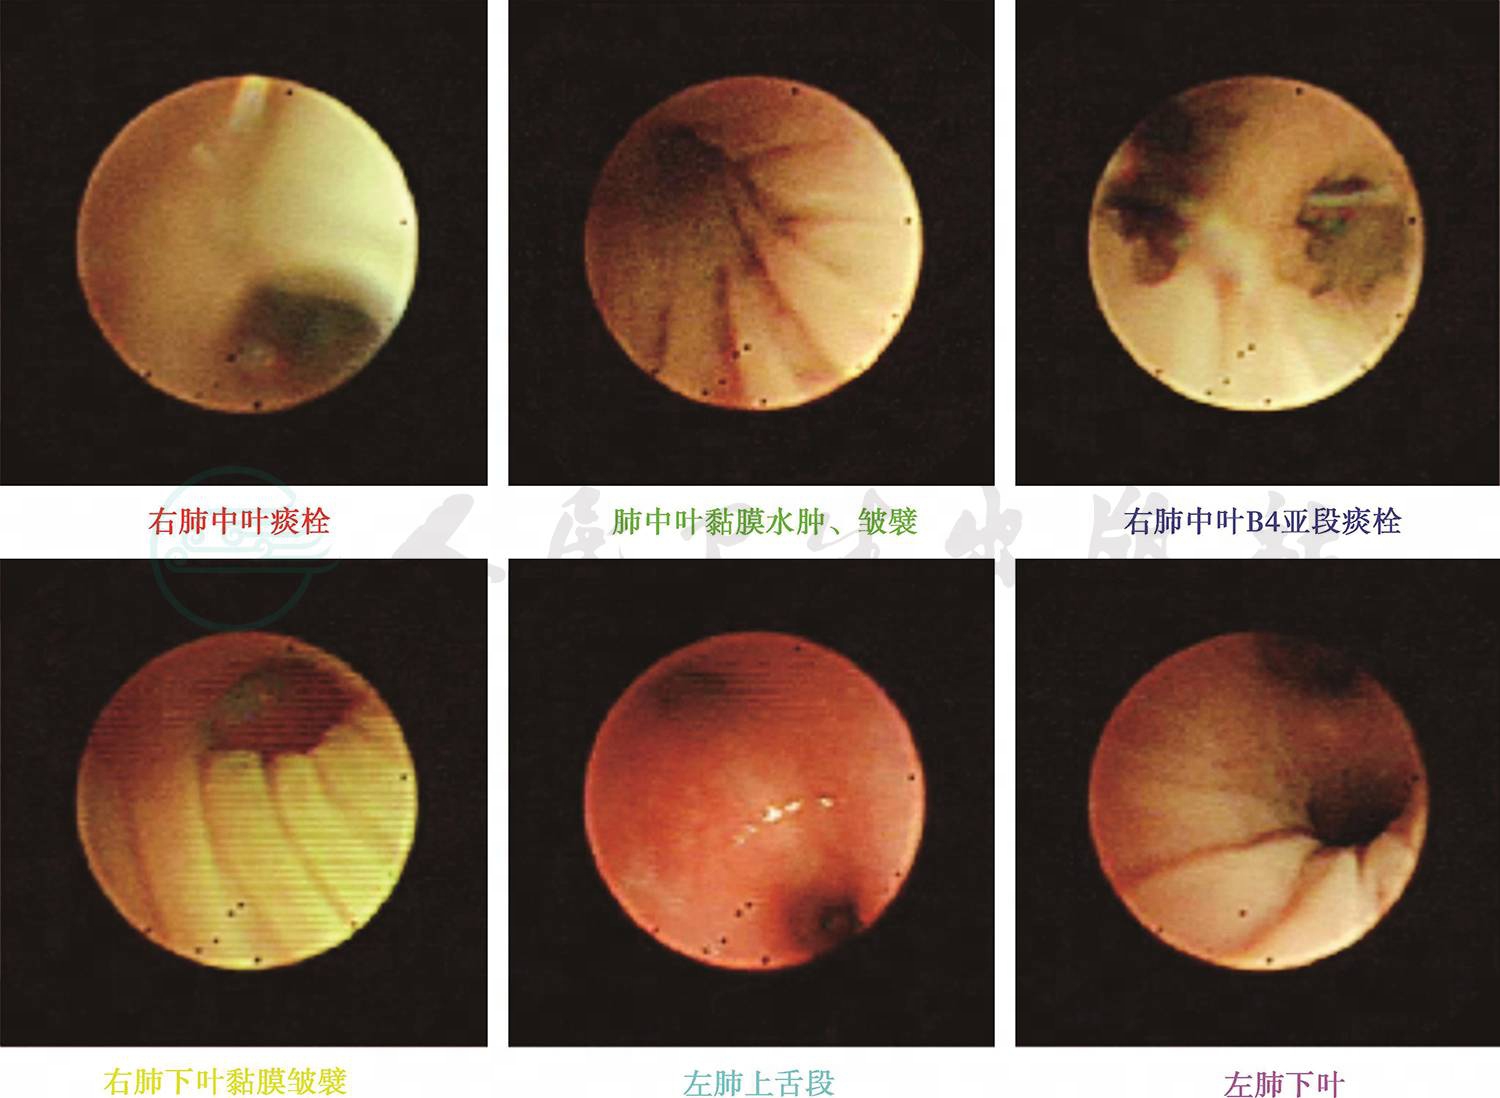

入院后完善相关检查:血常规:WBC 12.1×109/L,提示白细胞升高,以中性粒细胞为主;CRP 11.5mg/L(0~8mg/L);PCT 0.45ng/L(<0.05ng/L),ASO<25.0(0~200U/ml);ESR 12mm/h,均正常;病原学检测除肺炎支原体抗体(MPAb)1:40外,肺炎支原体抗体-IgM(MPAbIgM)阴性、鼻咽拭子肺炎支原体DNA测定阴性,肺炎衣原体抗体-IgM、常见呼吸道、肠道病毒及肝炎病毒检测均阴性。免疫球蛋白及淋巴细胞亚群均正常,除外免疫缺陷病。总IgE 38U/ml正常。尿便常规、肝肾功能、血气分析均正常。心电图正常,心脏、肝胆脾及肾脏彩超未发现异常。胸片(图4):双肺纹理增粗模糊,左肺上叶实变影,结合原有肺CT结果诊断急性支气管肺炎,左肺占位性质待定。考虑存在细菌感染,给予静脉滴注头孢呋辛钠100mg/(kg·d)抗感染,予祛痰止咳药物对症治疗。随后继续完善相关检查:血细菌培养未见细菌生长,痰细菌涂片及细菌培养为呼吸道正常菌群,真菌涂片及培养均阴性。结核抗体(TBAb)、结核菌素试验阴性,T-spot阴性,无结核感染依据。仅1,3-β葡聚糖23pg/ml略高,不除外真菌感染。头孢呋辛抗炎3天体温未见明显下降,升级抗生素至头孢吡肟后体温逐渐下降,咳嗽、喘息症状及肺部湿啰音及喘鸣音逐渐减轻,入院第10天体温恢复正常,仍有咳嗽及间断喘息;入院第15天,行肺CT+三维重建(图5)提示原有肺实变区液化、坏死,出现空腔阴影形成“新月形空气征”。入院第17天行纤维支气管镜检查(图6),结果:左、右肺各叶、段、亚段开口位置正常,黏膜充血、少许浆液性分泌物。除外先天性气道发育异常。BALF检查:一般细菌、结核菌及真菌涂片检查均未找到相应阳性菌,细菌培养未见细菌生长,PCR-TB阴性,真菌培养:25℃黑曲霉生长。追问病史:患儿有长期潮湿生霉环境接触史。诊断为曲霉菌肺炎(侵袭性肺曲霉菌病)。加用伊曲康唑口服[6~8mg/(kg·d)]、两性霉素B雾化吸入(2.5mg/次,2次/d)1周,咳嗽逐渐减轻,喘息症状及肺部喘鸣音消失后出院。

图6 入院17天行纤维支气管镜检查